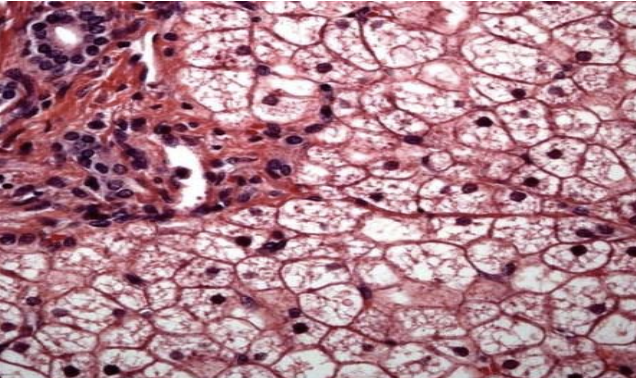

what does the image show?

amyloidosis